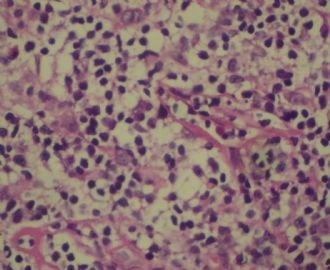

标本名称:  左前臂数个大小不等的皮下肿物。

• 左前臂数个大小不等的皮下肿物     淋巴瘤?图4

图4

病例不错。细胞胞浆透亮,间质血管丰富,图片不是很清晰,似乎有嗜酸粒细胞?

恶性,首先考虑T-NHL。IHC证实。

既往有NHL病史,图片不太清晰,细胞弥漫,胞浆透亮,首先考虑T细胞淋巴瘤。